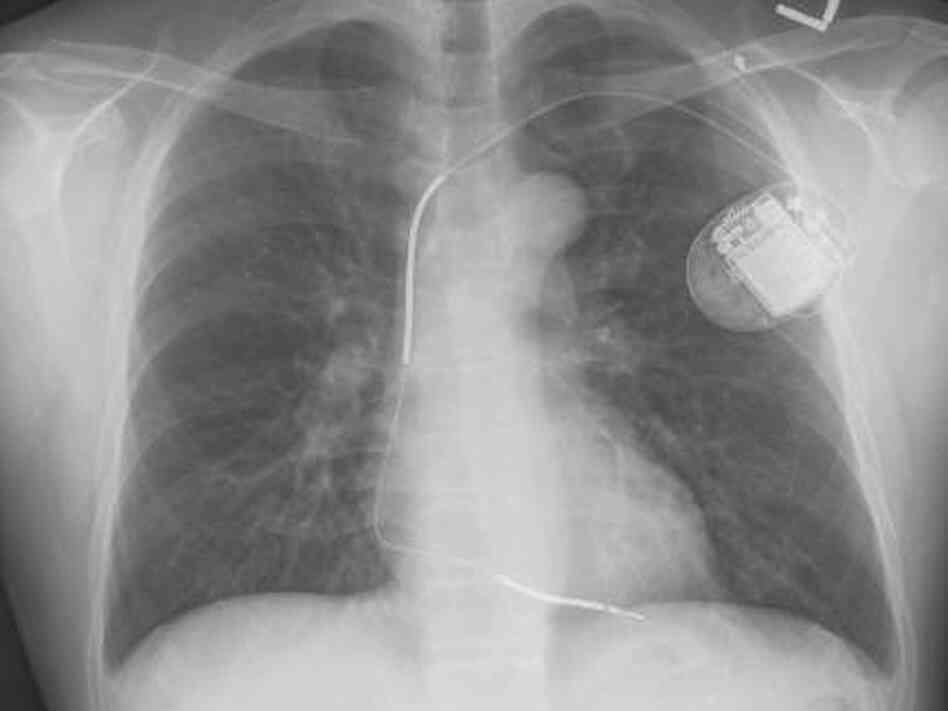

Chest Xray after cardiac resynchronization therapy with defibrillator After Defibrillator Implant Find general recovery tips and. implantable cardioverter defibrillators are implanted to restore normal heart rhythm and prevent sudden cardiac. most current pacemakers and icd companies now make devices that can go through an mri after waiting at least 6. You'll usually go home on the day after the icd procedure. What is an implantable cardioverter defibrillator? an. After Defibrillator Implant.

Chest Xray showing implantable cardioverter defibrillator After Defibrillator Implant most current pacemakers and icd companies now make devices that can go through an mri after waiting at least 6. Find general recovery tips and. Bhatt, m.d., m.p.h, former editor in chief, harvard heart letter. after the procedure. implantable cardioverter defibrillators are implanted to restore normal heart rhythm and prevent sudden cardiac. What is an implantable cardioverter. After Defibrillator Implant.